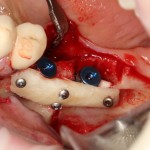

— сложнее, чем простая установка двух-трех имплантов:

Как, например, на картинке выше — тут и удаление, и остеопластика, и еще два импланта. Вот тут антибактериальная профилактика по-любому нужна.